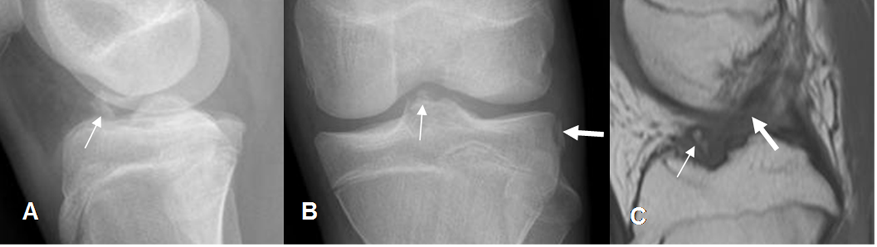

Fig 47. Avulsión de la espina tibial anterior.

A: Rx lateral y B: Rx AP. Fragmento óseo proyectado sobre la parte anterior de la articulación, en la línea media. En la proyección lateral existe adicionalmente, una fractura de Segond. (Flecha gruesa).

C: RM sagital en T1. Avulsión de la espina tibial anterior, con alteración en la orientación y señal del LCA, por ruptura. (Flecha gruesa).